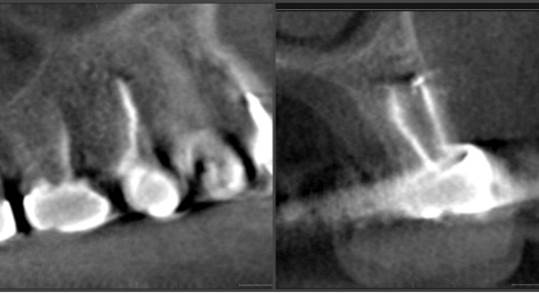

Clinical case: Extraction, immediate implant placement, & provisionalization

- Courtesy of Dr. Iulian Filipov, Romania -

Keywords

AnyRidge, R2GATE, guided surgery, immediate placement, immediate provisionalization, initial stability, Dr. Iulian Filipov, #25, maxillary posterior, immediate loading, Mega ISQ

“AnyRidge & R2GATE show stable results

after immediate extraction, immediate implant placement, & immediate loading,

even with low bone density.”